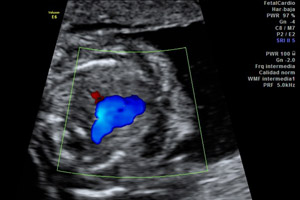

En la ecografía de la semana 18 se visualizan las cuatro cámaras cardiacas y mediante una ecografía Doppler se puede ver el recorrido de todos los vasos sanguíneos del cuerpo del bebé. Podemos ver también cómo se chupa el dedo, cómo bosteza e incluso cómo sonríe.

Ecografía Doppler de la semana 18. En esta imagen ecográfica se visualiza un corte del corazón fetal, empleando la tecnología del Doppler color.